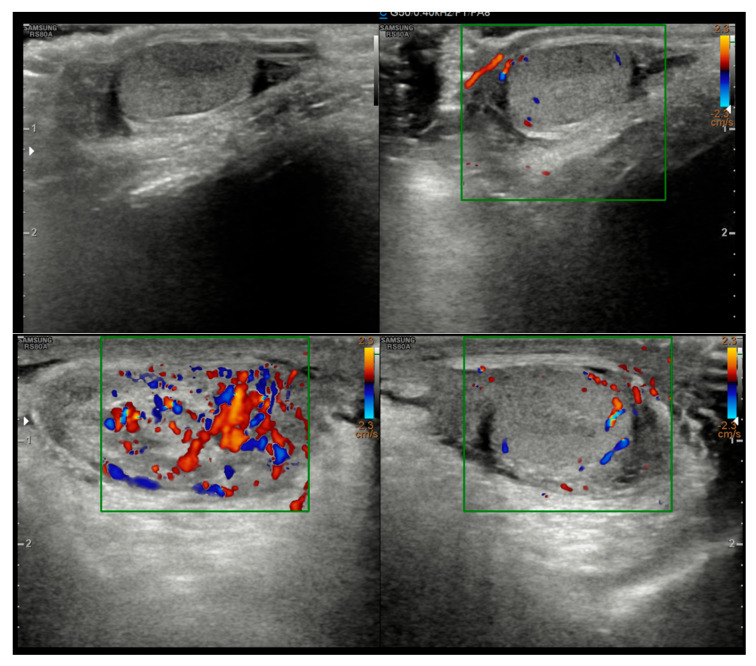

我们报告的情况下,一个5岁的男孩从一个斯里兰卡移民家庭在卡塔尼亚,意大利,诊断为Dirofilaria再感染精索。患儿表现为左侧腹股沟疼痛和肿胀。初步评价提示是睾丸附睾炎,用阿莫西林/克拉维酸盐和非甾体抗炎药治疗不成功。当症状加重时,考虑Morgagni棘球体扭转。探查性手术发现左侧精索有一个坚固的肿块。切除病变的组织病理学检查显示肉芽肿性炎症反应中有蠕虫碎片。随后的PCR分析检测到D. repens DNA。手术切除肿块后,病人完全康复。鉴于人类双丝虫病发病率的增加,在鉴别诊断不明原因的皮下或腹股沟结节时应考虑repens,特别是在有相关旅行史的患者中。该病例强调了准确诊断的重要性,以避免不必要的侵入性手术或延长抗菌药物治疗。这是意大利报告的最年轻的生殖器感染儿科病例之一,意大利占欧洲病例的一半。

We report the case of a 5-year-old boy from a Sri Lankan migrant family in Catania, Italy, diagnosed with a Dirofilaria repens infection in the spermatic cord. The child presented with pain and swelling in the left inguinal area. Initial evaluation suggested orchiepididymitis, which was treated unsuccessfully with amoxicillin/clavulanate and NSAIDs. As symptoms worsened, torsion of the Morgagni hydatid was considered. An exploratory surgery revealed a firm mass in the left spermatic cord. Histopathological examination of the excised lesion showed fragments of a helminth within a granulomatous inflammatory reaction. Subsequent PCR analysis detected D. repens DNA. The patient fully recovered after surgical excision of the mass. Given the increasing incidence of human dirofilariasis, D. repens should be considered in the differential diagnosis of unexplained subcutaneous or inguinal nodules, especially in patients with a relevant travel history. This case highlights the importance of accurate diagnosis to avoid unnecessary invasive procedures or prolonged antimicrobial therapies. It represents one of the youngest pediatric cases with genital involvement reported in Italy, a country that accounts for half of the cases in Europe.